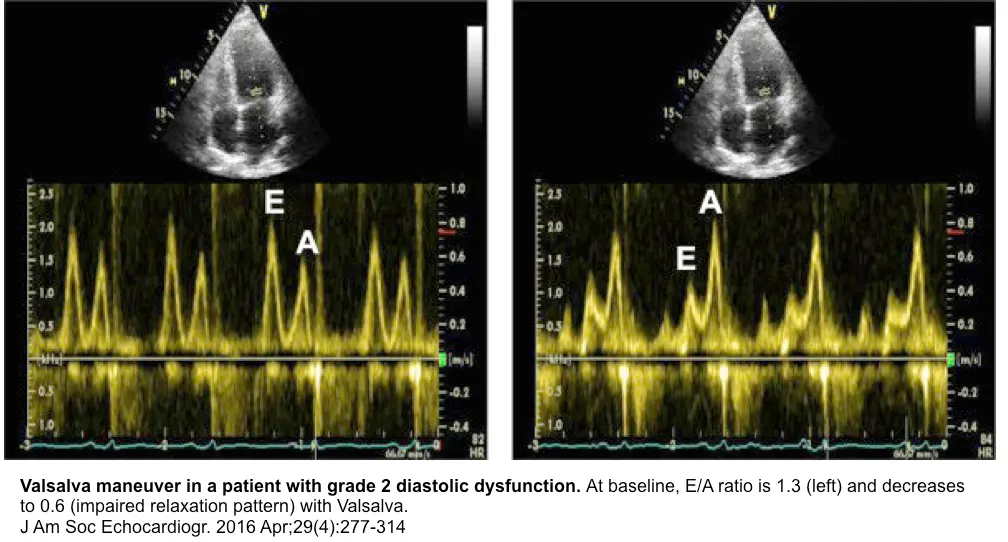

- The E/A ratio in healthy, euvolemic, recumbent young adults is typically >1. When τ is prolonged (often seen with aging, HTN, HCM, ischemia, AMI), is lower, and the E-wave is smaller, leading to the grade I diastolic dysfunction filling pattern where E/A <1.

- To compensate for impaired relaxation, LA pressure may rise, increasing and E-wave height, leading to the grade II (“pseudonormal”) or grade III (“restrictive”) diastolic dysfunction filling pattern, with consequent risk for pulmonary congestion

- Valsalva maneuver to tease out normal vs “pseudonormal” (grade II) diastolic dysfunction

- tbh, this is an old school 👵 approach, so you may rarely have a sonographer collect this for you

- normal: Valsalva → ↓ preload → ↓ amplitude of both the E- and A-wave

- grade II diastolic dysfunction: Valsalva → ↓ preload → filling will occur on the flatter portion of the LV diastolic PV relationship; ∴, E-wave amplitude ↓ > A-wave amplitude ↓ less (or may actually ↑) → E/A reversal (i.e., E/A ratio <1)